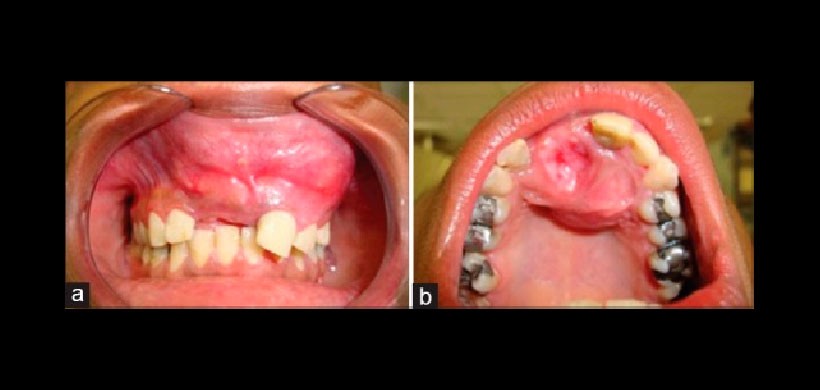

Figura 2: (A y b) El examen intraoral mostró un tumor en la región maxilar anterior que obliteraba el surco vestibular anterior. La mucosa palatina en la región del diente 11 se mostró ulcerada debido a la fricción masticatoria